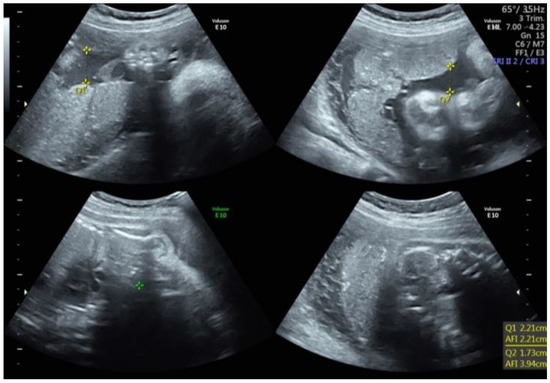

An AFI less than or equal to 5 cm, or the absence of an SVDP measuring at least 2 cm, is typically used to diagnose oligohydramnios (Figure 1) [12,35]. Anhydramnios is the term used to describe a complete or near-complete lack of amniotic fluid. The prevalence of oligohydramnios varies widely, from approximately 0.5% to 5% of singleton pregnancies, depending on the study population and the diagnostic criteria [32].

Figure 1.

Oligohydramnios. Q: quadrant. AFI: Amniotic Fluid Index.